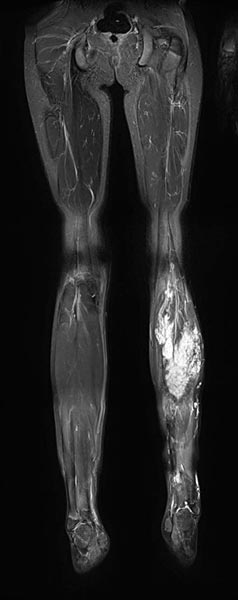

In der T2-gewichteten, fettunterdrückten koronaren MRT ist die FAVA als hyperintense Läsion im linken Musculus gastrocnemius sichtbar.

Bei der Fibro-Adipose Vascular Anomaly (FAVA) handelt es sich um eine intramuskulär gelegene, oft progressiv mit Bindegewebsproliferation einhergehende Variante der venösen Malformation. Die gesamte FAVA konnte in diesem Fall operativ entfernt werden. Aufgrund der starken Manipulation an einem Nerv, der langstreckig von der Malformation eingemauert war, kam es postoperativ zu einem Ausfall dessen. Der Nerv erholte sich bei dieser Patientin jedoch ohne weitere operative Maßnahmen.